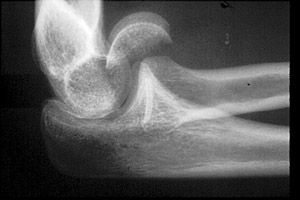

- Click on the image for a larger versionALateral radiograph of the elbow. This demonstrates a fracture of the capitellum.